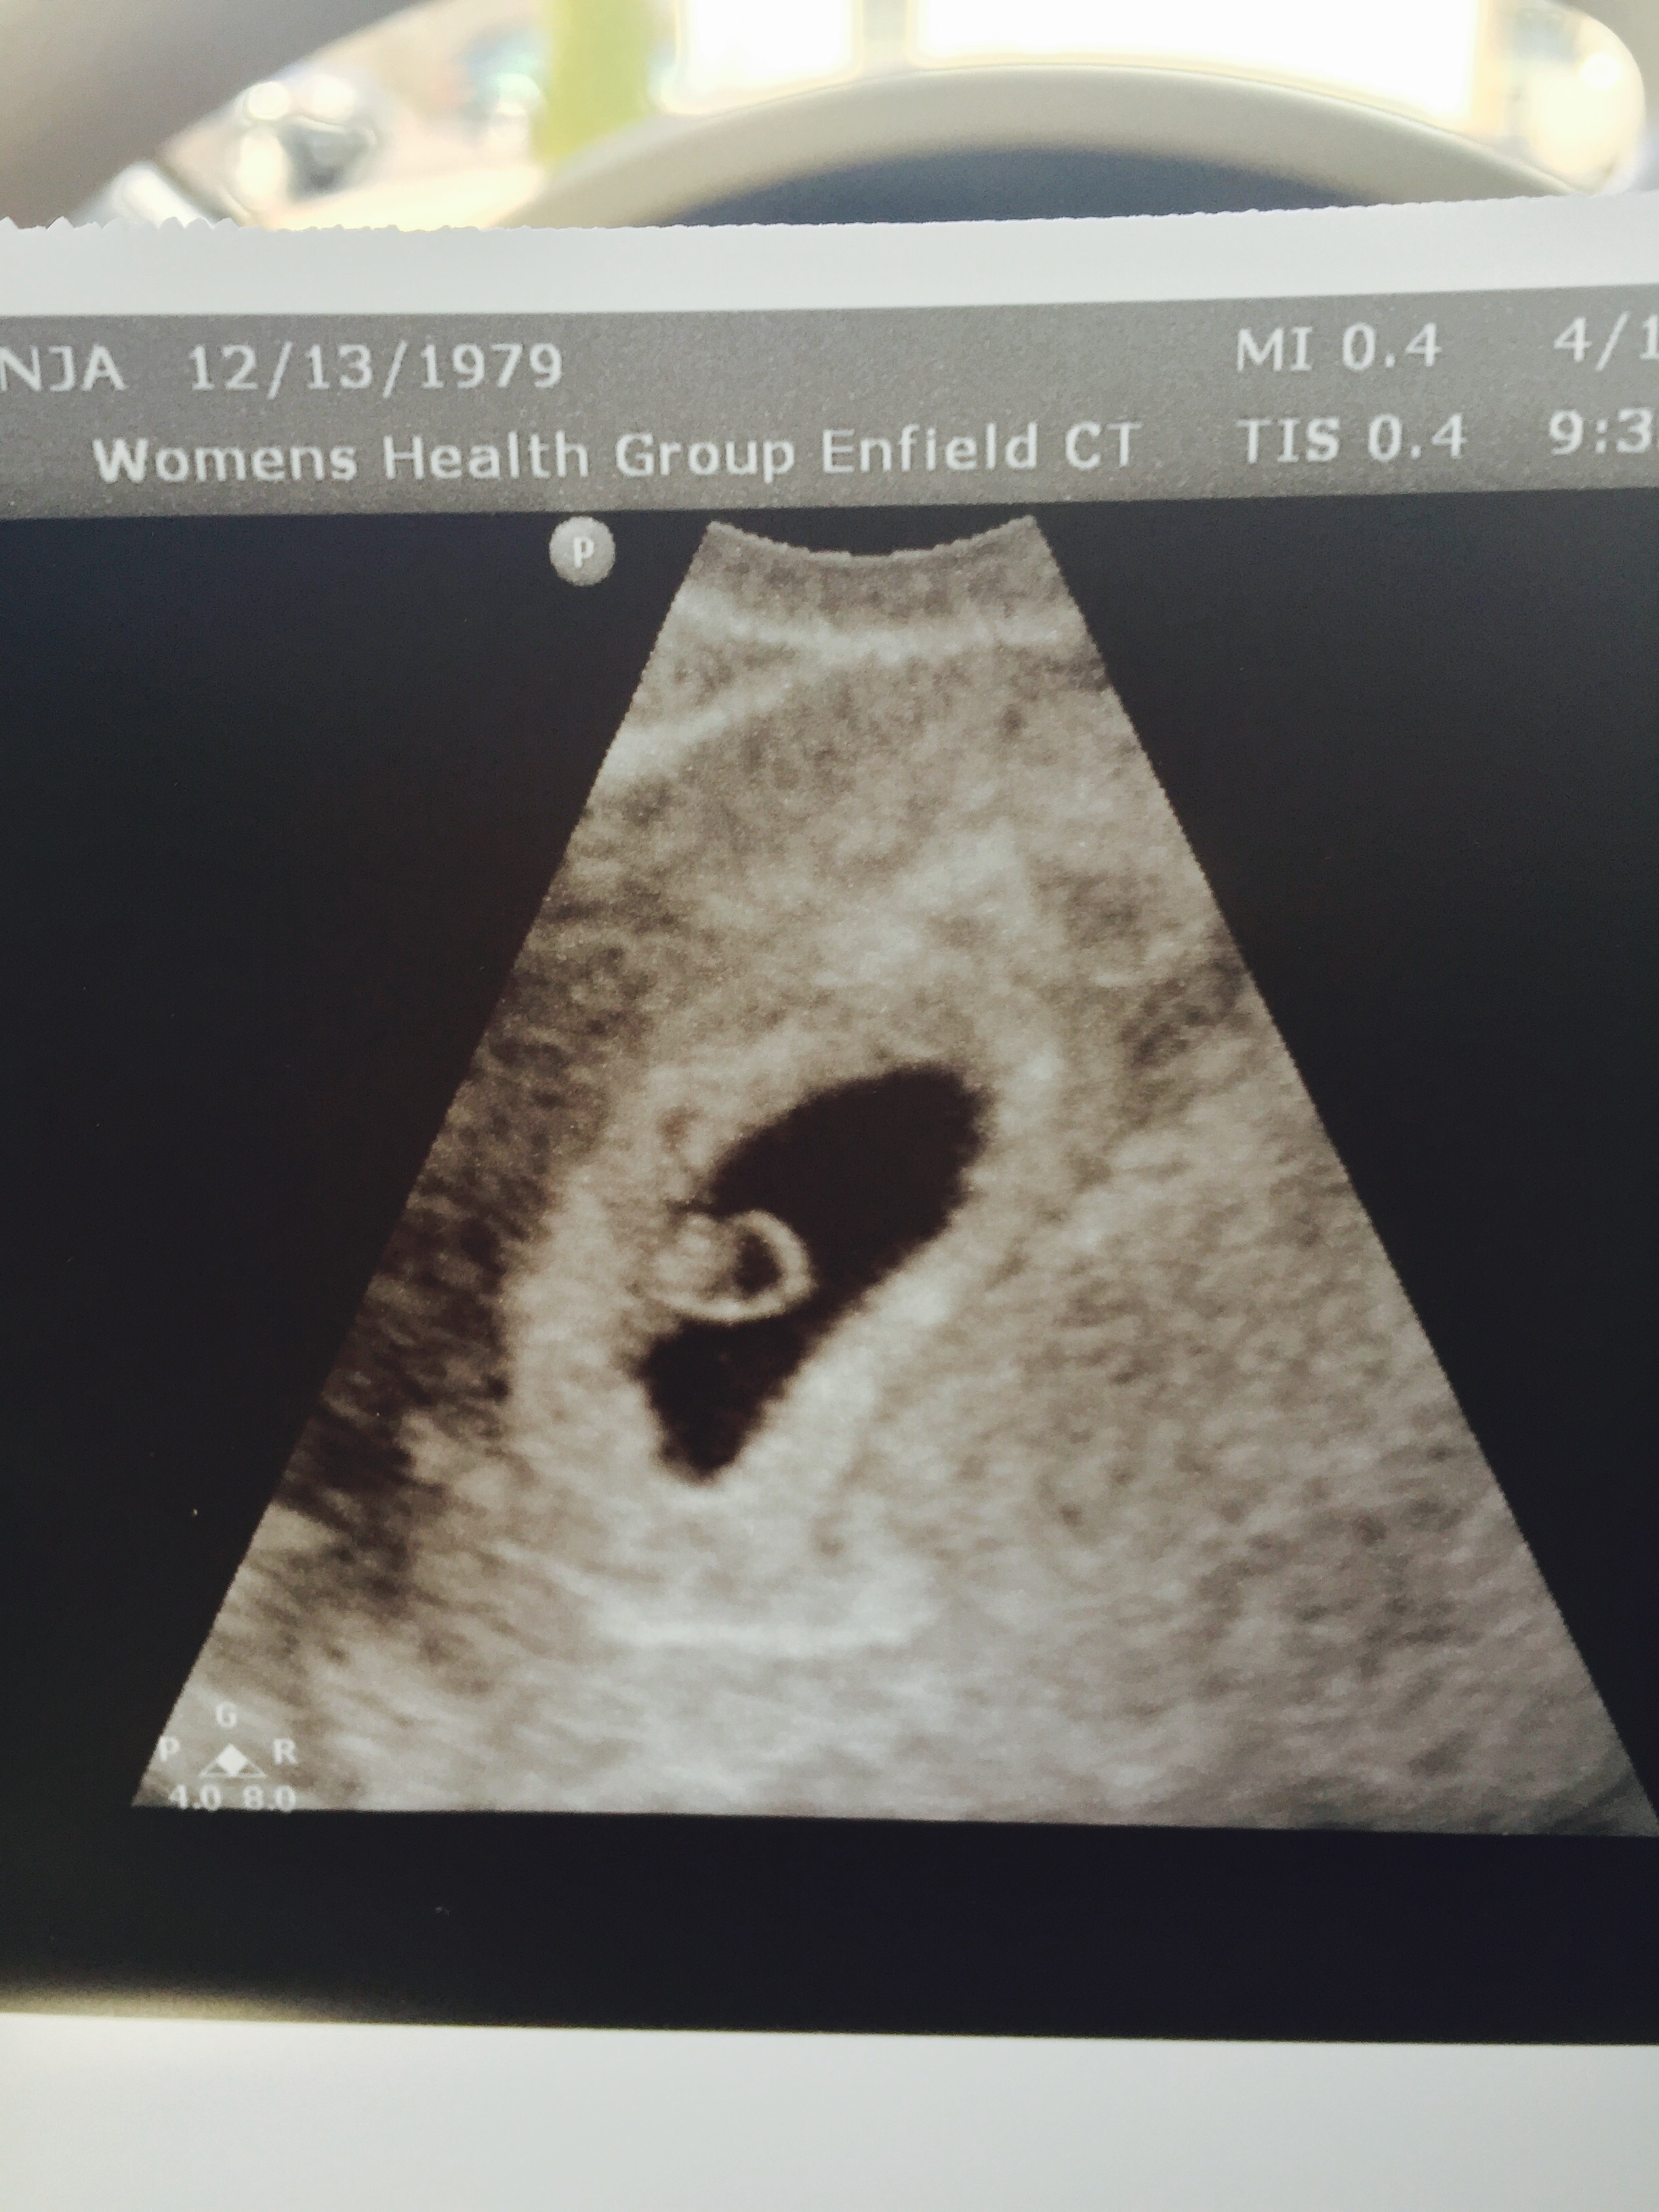

Yesterday had our first appt, 6w3d, and I told my dr about some cramping I am having on my right side. So she popped us in another room for a quick ultrasound to check things out and we saw a flicker of a heartbeat for the first time. Pretty amazing!

This is my 3rd pregnancy, have 2 DS, so I scheduled the nurses visit appointment on week 10 may 6th. They said they'll do it to check heartbeat(s) then. They did one yesterday though because I feared I was having a miscarriage. Didn't see much but know the sac is healthy and all is well!

I'm having my first at 8 weeks, my doctor said since I had an early loss last time he wants me to see it, so I can try and relax a little bit they normally wouldn't do it until 12 weeks.

Mine is tomorrow, April 17th. Having two previous losses, I'll only be at 6w6d but my OB said my hcg is high enough to check out what's in there. Fingers and toes will be crossed!